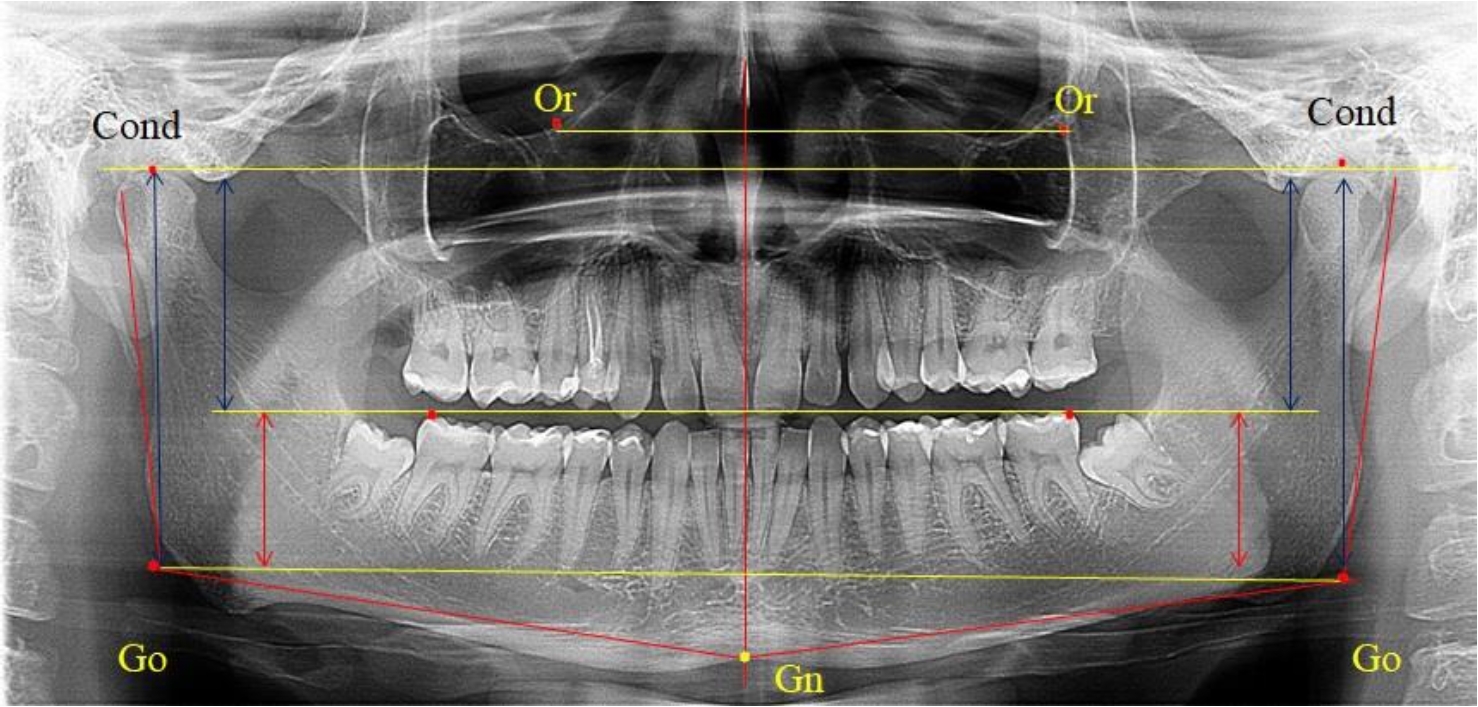

3-я подгруппа была с наименьшим количеством анализируемого материала, и здесь было проанализировано 17 комплектов рентгенограмм [(22,97 ± 4,89) %], на которых средняя величина отношения верхней части ветви к нижней составляла 2,45 ± 0,04, что было достоверно больше показателя, полученного по группе в среднем, а также в 1-й и 2-й подгруппе. Визуально параметры ветви отличались от других подгрупп. Высота ветви составляла (57,83 ± 0,89) мм, что было несколько меньше, чем в других подгруппах. Максимальная высота была 64 мм, а минимальная – 53 мм. Высота верхней части составляла (41,03 ± 0,59) мм, что было близким по значениям, полученным в других подгруппах и свидетельствовало о меньшей вариабельности указанного параметра. В то же время высота нижнего отдела ветви была (16,83 ± 0,36) мм и показатель отличался в меньшую сторону, по сравнению с аналогичным размеров в других подгруппах (рис. 4).

Рис. 4. ОПТГ пациента 3-й группы с увеличенным коэффициентом соотношения частей ветви нижней челюсти